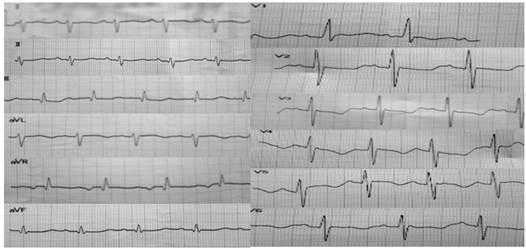

Через месяц, в возрасте 1 месяца 10 дней ребенок госпитализирован в плановом порядке в ДРКБ с жалобами на эпизоды учащенного дыхания. Объективно состояние оценено как тяжелое за счет симптомов сердечной недостаточности, неврологической симптоматики. Кожный покров бледно-розовый, цианоз носогубного треугольника, акроцианоз. Пастозности и отеков мягких тканей не отмечается. Мышечный тонус снижен. Рефлексы новорожденного вызываются слабо. Аускультативно дыхание пуэрильное, проводится по всем легочным полям, ЧД 50 в минуту. Тоны сердца ясные, ритм правильный. ЧСС 146 уд/мин. При пальпации живот мягкий, не вздут, печень, селезенка не увеличены. Стул самостоятельный. Мочеиспускание не нарушено. Выполнено диагностическое обследование. В общем анализе крови без отклонений: лейкоциты 9,6х109/л, сегментоядерные 23%, лимфоциты 68%, моноциты 9%, эритроциты 4,5х1012/л, гемоглобин 128 г/л, тромбоциты 337х109/л. В биохимическом анализе крови отмечаются: гипопротеинемия - 57,8 г/л (норма 66-88 г/л), повышение уровня АСТ до 48,9 ед/л (норма до 37 ед/л), общего билирубина до 105,53 мкмоль/л (норма 20,5 мкмоль/л), щелочной фосфатазы до 585,19 ед/л (норма 64-306 ед/л). На ЭКГ регистрируются синусовый ритм, отклонение электрической оси сердца вправо, перегрузка правого желудочка (ПЖ) (рис. 3).

Рис. 3. ЭКГ: синусовый ритм, отклонение электрической оси сердца вправо, перегрузка правого желудочка